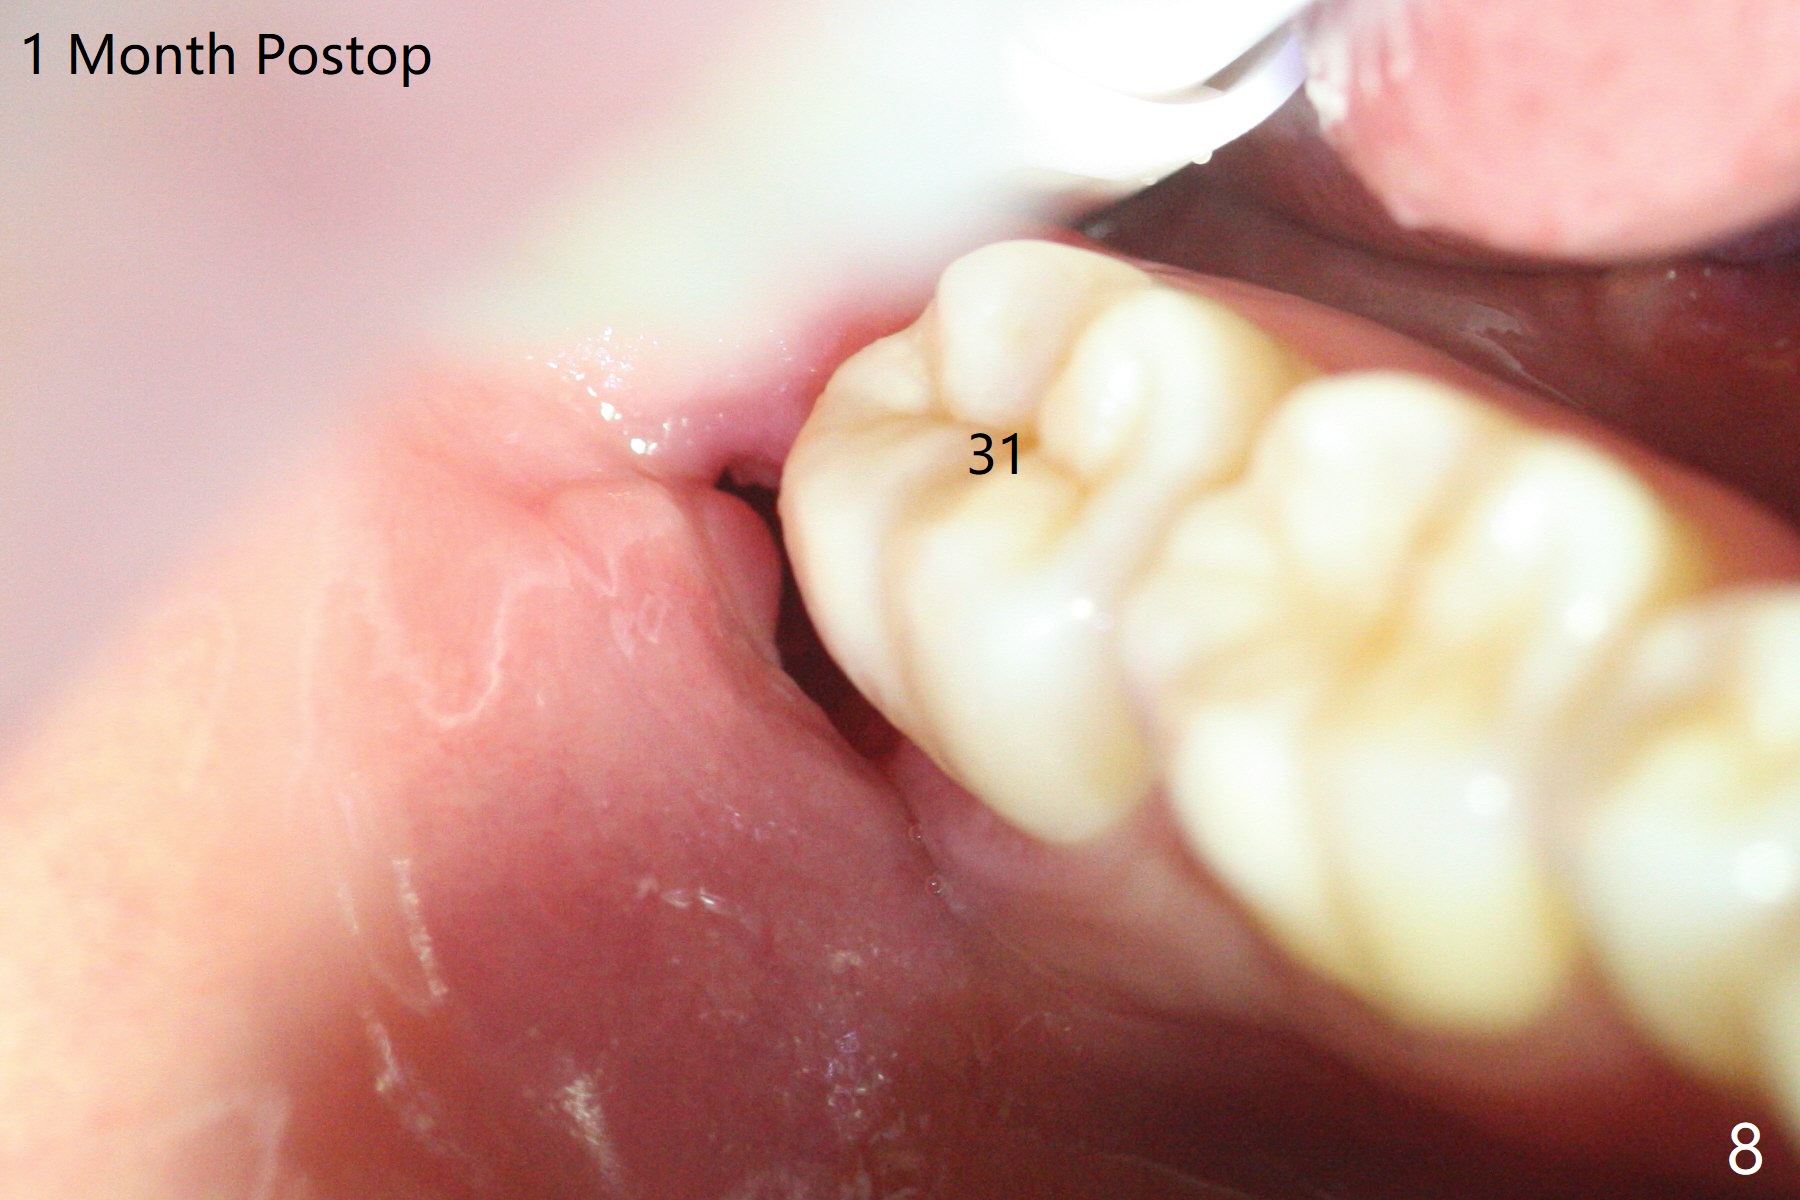

In fact the tooth #32 is extracted first; the defect involves the distobuccal aspect of the tooth #31 (Fig.4 *). An intraop PA is taken after extraction to confirm whether a broken surgical fissure bur tip retains or not; the distal lamina dura of #31 is low (Fig.5 *). It is expected to increase after cocktail bone graft (Fig.5' arrow). As planned, the bone cement (Fig.6 C) and allograft (G) are placed in the distal and mesial portions of the socket; between them is Osteogen Plug (O). Another piece of Osteogen Plug (as collagen membrane for bone graft) is placed on the top of the socket before suturing with 4-0 Plain Gut (Fig.7,7' O). Also note the bone graft being placed distobuccal (CT study) to #31 (Fig.7' red dashed line) to reduce possibility of future periodontitis. The patient returns 15 days postop with chief complaint of mild pain since extraction, although the wound looks normal. The transverse cortex connecting to the lamina dura (Fig.5 *) is obliterated when allograft is placed (Fig.7 G). The part of the graft remains in place 1 month postop (Fig.9) in spite of wound dehiscence (Fig.8). The bone graft loss is indicated by the fact of the reappearance of the transverse cortex (Fig.9). In the same appointment, the tooth #17 (Fig.10) is being extracted (Fig.11), leaving a defect mesiobuccal (Fig.12 *) to distal (curette). Part of Osteogen plug (Fig.13 O) is stretched to cover the mesially placed allograft (Fig.14 G). One quarter of Collagen plug is placed over the Osteogen plug (Fig.13 O) before 4-0 PGA suturing. There is bone regeneration 1 year postop (Fig.15,16).